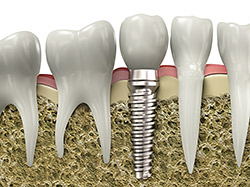

An implant is a synthetic tooth root in the shape of a post that is surgically placed into the jawbone. The “root” is usually made of titanium, the same material used in many replacement hips and knees, and a metal well suited to pairing with human bone. A replacement tooth is then fixed to the post. The tooth can either be permanently attached or removable. Permanent teeth are more stable and feel more like natural teeth.